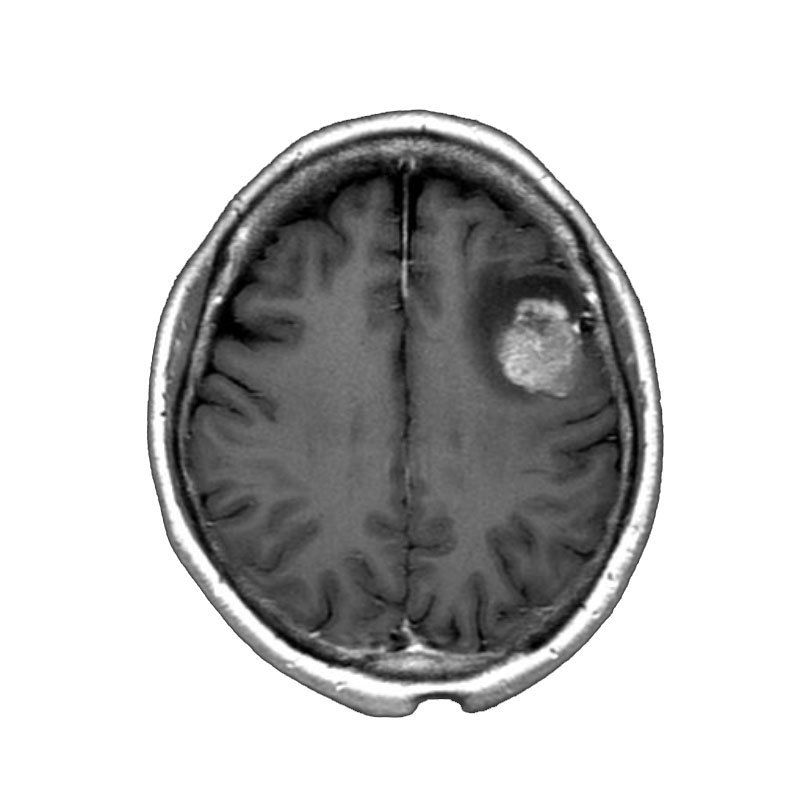

右側頭葉脳腫瘍

摘出術

南田/野本/佐伯